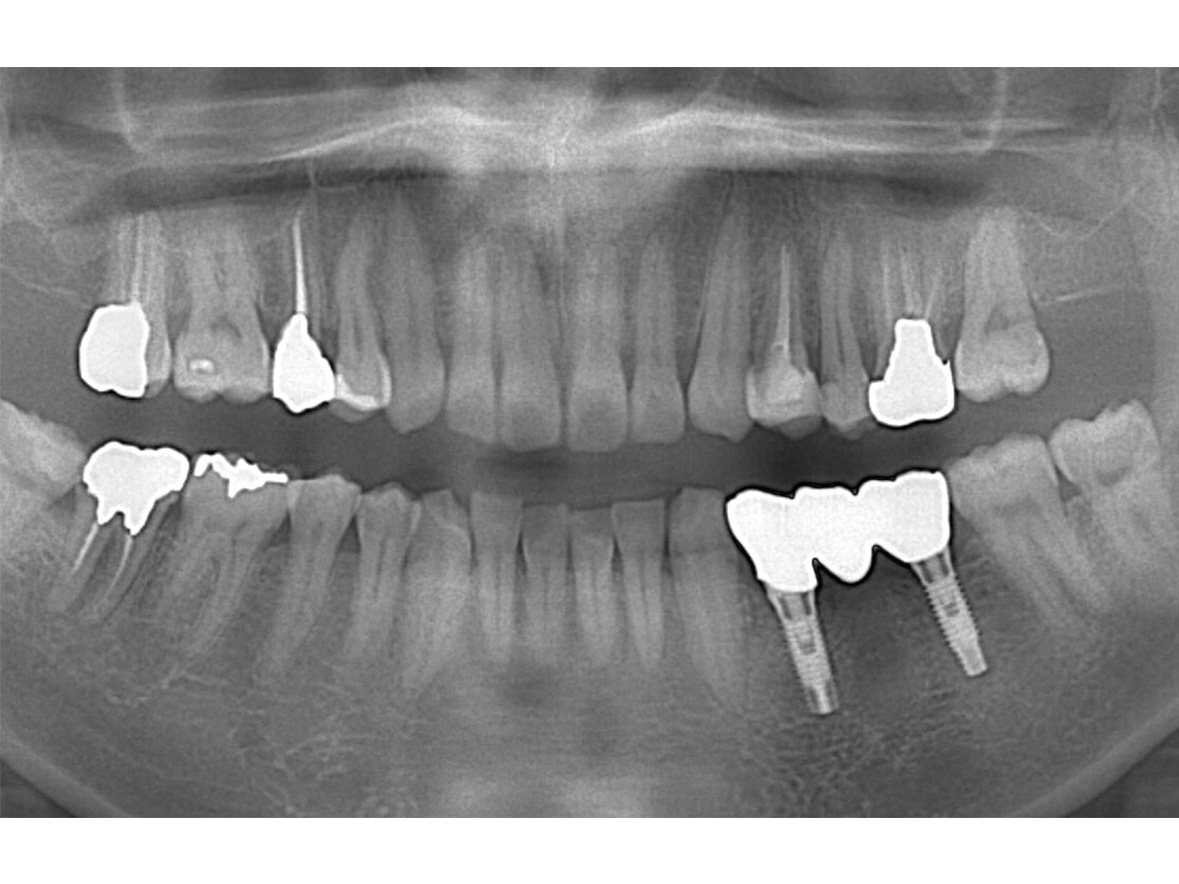

症例3

患者様の年齢 60代男性 主訴 歯が痛い 治療内容 左下456インプラント治療

抜歯即時インプラント埋入後3ヶ月の待機期間後、ジルコニアによる上部構造装着費用 77万円 治療期間・通院回数 4ヶ月/5回 デメリット・リスク 外科処置に伴う痛み・腫れ・出血・合併症の可能性があります。 -